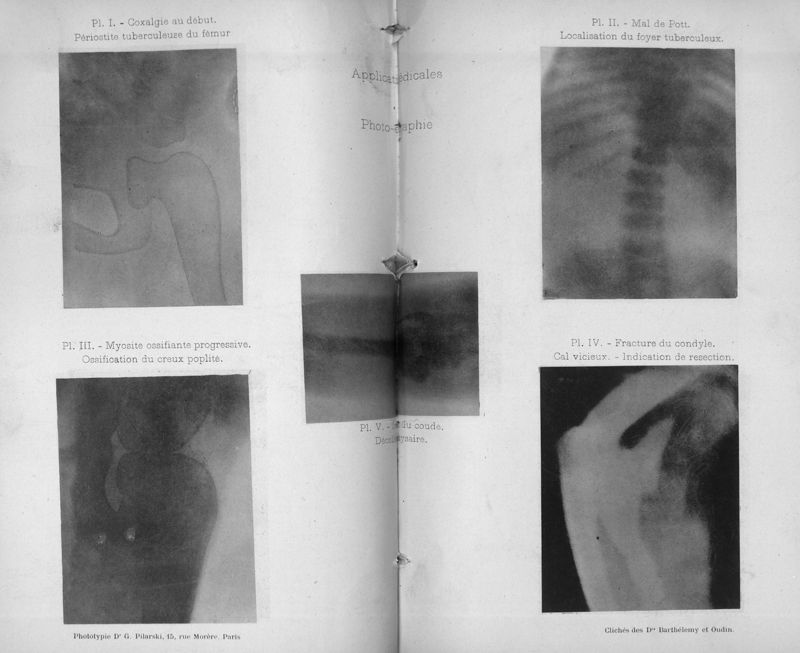

Barthélemy, Toussaint / Oudin, Paul .

Applications de la méthode Röntgen aux sciences médicales : communications aux congrès de Nancy et de Londres (août 1896)

Paris : Masson & Cie ; Nancy : A. Crépin-Leblond, 1896.